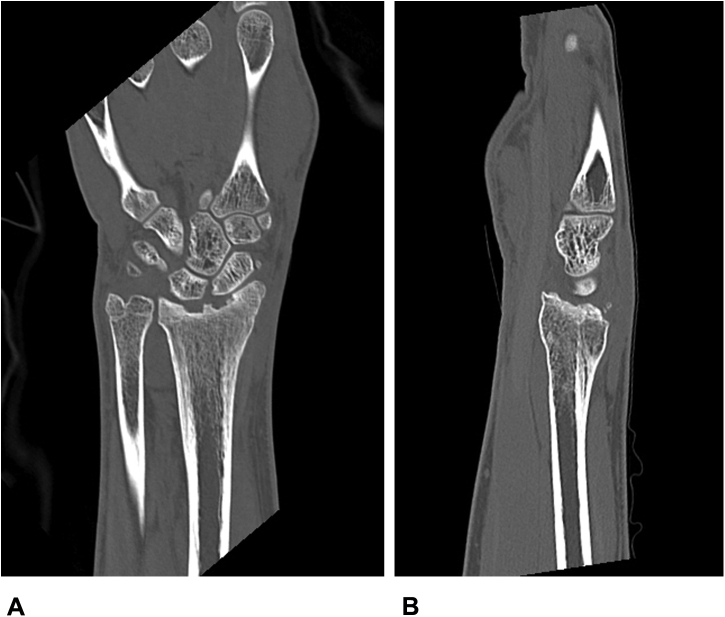

At the time of presentation, he complained of pain and swelling in the right wrist. He had limited active and passive motion, with 20° of flexion and 15° of dorsiflexion, and had pain with any motion in the wrist. His pronation was 60° and supination 75°. Plain radiographs taken at that time showed degenerative changes in the radiocarpal joint, with loss of volar tilt (Fig. 2). Radial inclination on these images was 13°, volar tilt was -12°, and ulnar variance was +3 mm. Further imaging was done with computerized tomographic scans to evaluate the malunion and magnetic resonance imaging (MRI) to evaluate the state of his cartilage (Figs. 3, 4). These images confirmed a large defect in the articular surface of the distal radius, involving part of the lunate and scaphoid fossae, while the cartilage on the carpal bones appeared to be intact. Due to the patient’s age, consideration was given to the possibility of a vascularized osteochondral graft, but on further research, none of the described donor sites appeared to offer the right size6 or concavity7 to reconstruct the involved segment. Comparing x-rays of his great toe and the defect in the distal radius showed that the articular surface of the proximal phalanx at the metatarsophalangeal joint potentially offered such a graft. This option was discussed at length with the patient and his mother, who agreed to undertake an attempt at reconstruction of his wrist with a vascularized graft from the great toe.

Figure 3.

A Representative view of the right wrist on CT scan. B Representative view of the right wrist on CT scan. CT, computerized tomography.